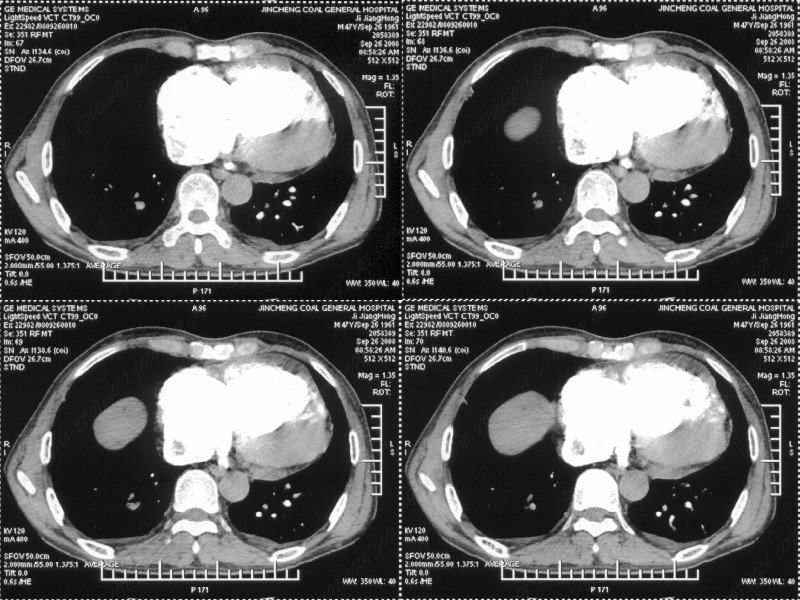

男性,47岁。胸部不适一年,ct检查发现右胸膜下结节。http://www.radida.com/bbs/forum.php?mod=viewthread&tid=46094

汇报临床诊断:右肺动脉分枝栓塞

考虑心脏疾患引起的右侧斜裂增厚。

右肺静脉充盈缺损,左心房体积小,右肺动脉远端动脉充盈缺损,右肺血管影细小,考虑;右肺动脉远端栓塞.

右肺中叶外侧段占位,考虑周围型肺癌伴局限性肺气肿,不除外炎性假瘤